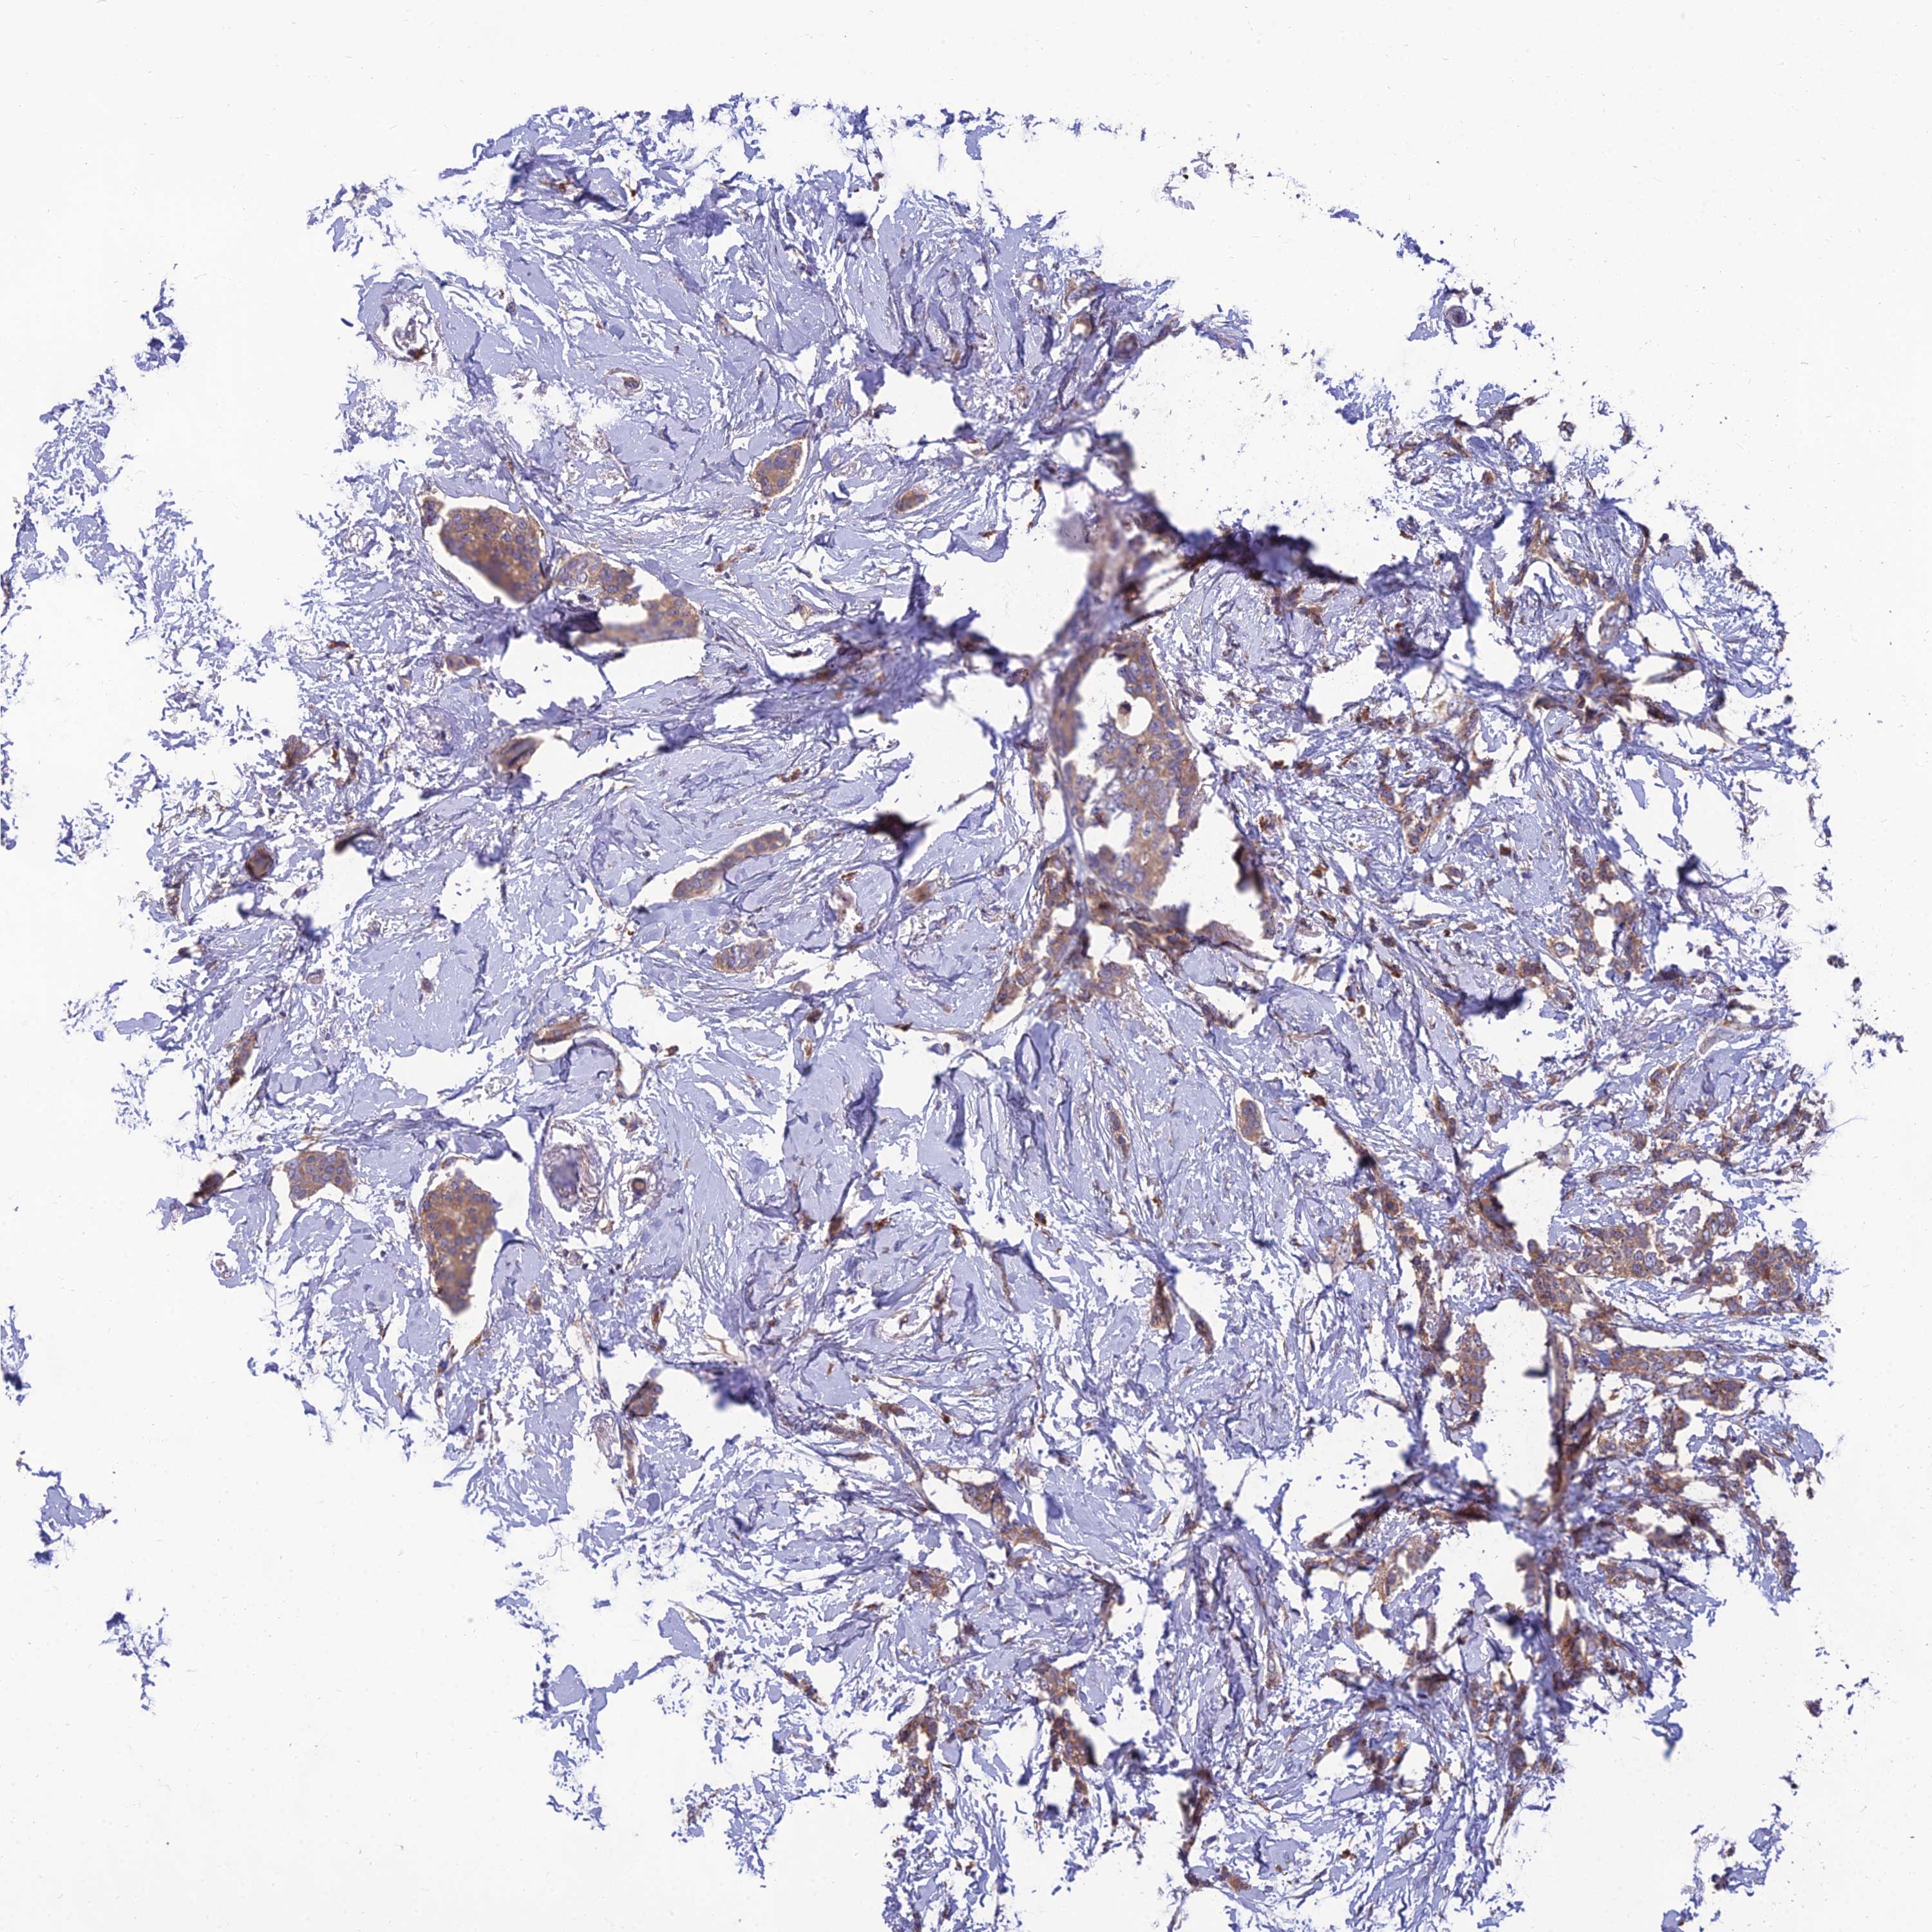

CANCER BREAST CANCER Show tissue menu

BRCA TCGA BRCA VALIDATION PROTEIN EXPRESSION